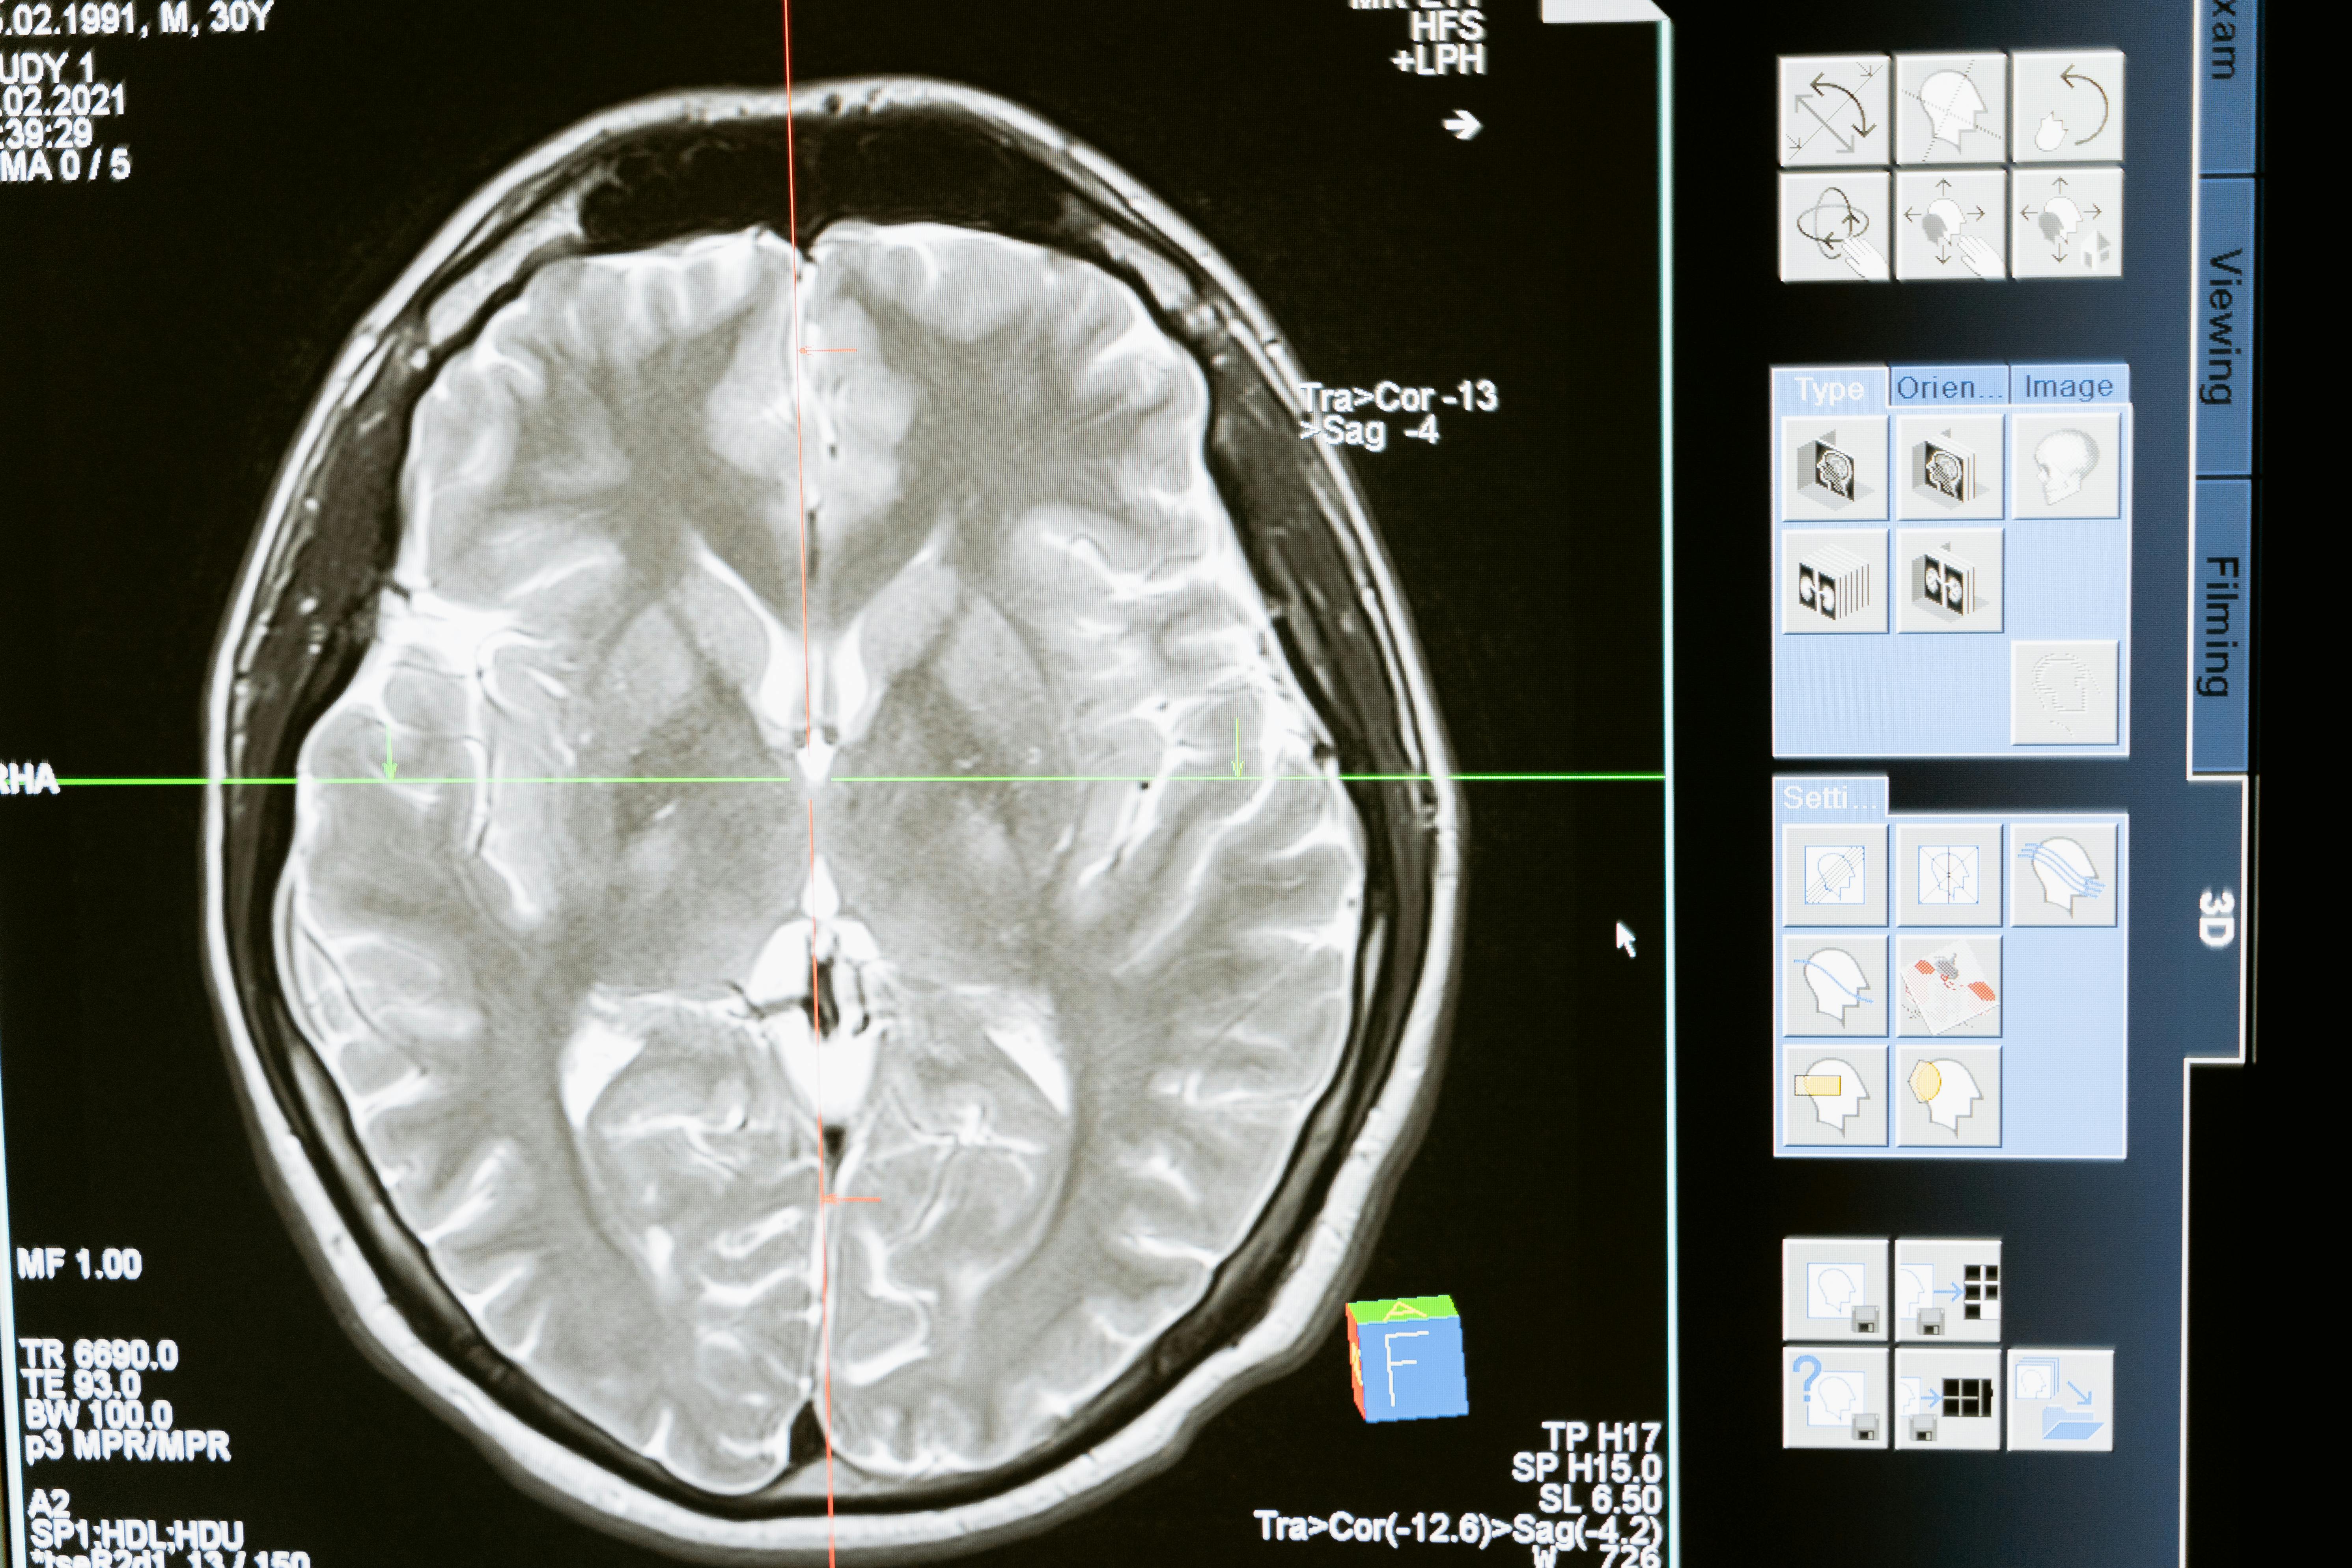

뇌졸중은 뇌에 혈류 공급이 차단되거나 혈관이 터지면서 뇌조직이 손상되는 병이에요. 크게 **허혈성(뇌경색)**과 **출혈성(뇌출혈)**으로 나뉘며, 발병 원인은 고혈압, 당뇨, 고지혈증, 심장질환 등이 있어요.

중요한 건, 뇌는 한 번 손상되면 되돌릴 수 없다는 점이에요. 그래서 증상이 생겼을 때 얼마나 빠르게 대응하느냐가 생명은 물론 후유증을 최소화하는 데 절대적으로 중요해요.